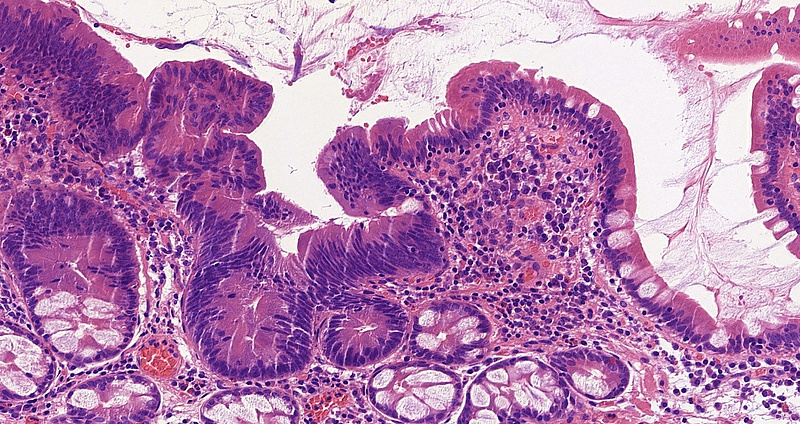

A 60-year-old female patient underwent multiple gastroscopies during the last 5 years because of recurring jaundice. Biopsy samples of the Vater papilla were taken each time, showing tubular or tubulovillous adenomatous growth. In 2021, the lesion was resected in toto with sphincteroplasty. Microscopic examination of this sample revealed tubular and tubulovillous structures, showing signs of low-grade dysplasia (revised Vienna classification category 3) in continuation with normal mucosa [Panels A-D]. Brunner glands were present in the submucosa. Even though the resection margin was free of dysplasia and invasive malignancy not detected, careful follow-up was recommended due to the patient’s history and the recurring nature of the lesion.